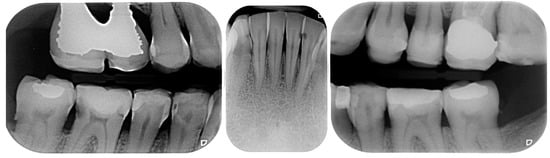

2.2. Clinical Example

2.3. Outcome Achieved